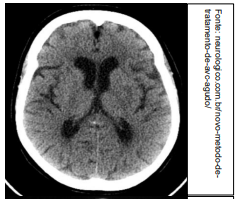

Um médico está atendendo Laura, estudante que retorna às aulas após internação recente em UTI por acidente vascular cerebral (AVC). No relatório de alta, consta que ela apresentou AVC tipo Hemorragia Subaracnoide Aneurismática, e há uma cópia da tomografia computadorizada de crânio, sem contraste, realizada pela paciente na admissão. A imagem que melhor corresponde ao achado do exame de imagem de Laura é: